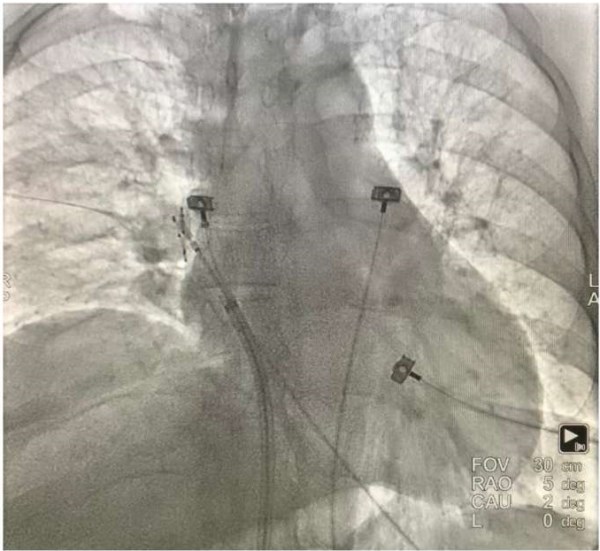

Повреждение стенки сердца, аорты и ЛВ. Гемоперикард

Рис. 4. Гемоперикард в ходе катетерной аблации. Определяется «двойной контур» сердца, свидетельствующий о наличии жидкости в полости перикарда.